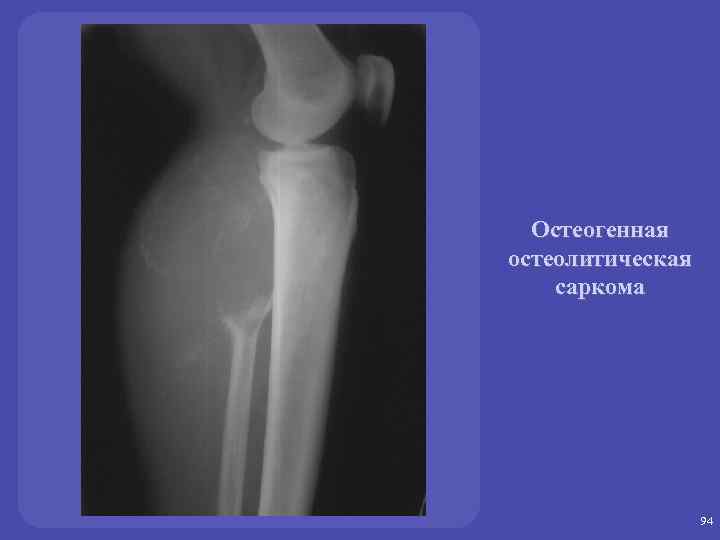

ЗЛОКАЧЕСТВЕННЫЕ ОПУХОЛИ: Остеогенная саркома - остеолитическая - остеобластическая Новообразование: -без четких наружных контуров - с наличием мягкотканного компонента 89

Остоегенная саркома остеолитическая и остоебластическая. üЛокализация зона активного роста – метафиз, метадиафиз длинных трубчатых костей. Изолированно диафиз не поражается. Через хрящ не переходит. üКозырек Кодмена – реактивный периостит. Спикулообразный периостит – костеобразование по ходу стенок кровеносных сосудов, проникающих в кость.

Остеогенная остеолитическая саркома 91

Остеогенная остеолитическая саркома 94